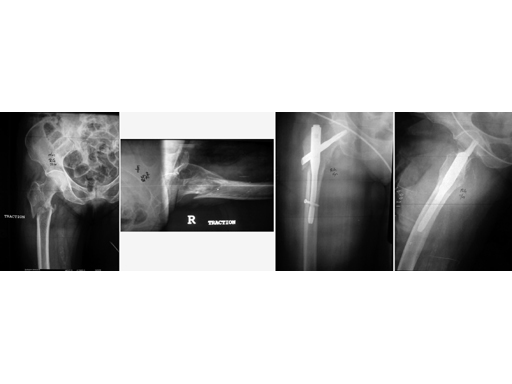

72-year-old female who sustained a closed intertrochanteric fracture in a car accident. The fracture was classified as an 31-A3-1. There were no other injuries reported.

Case provided by Cliff Turen, Macon, USA